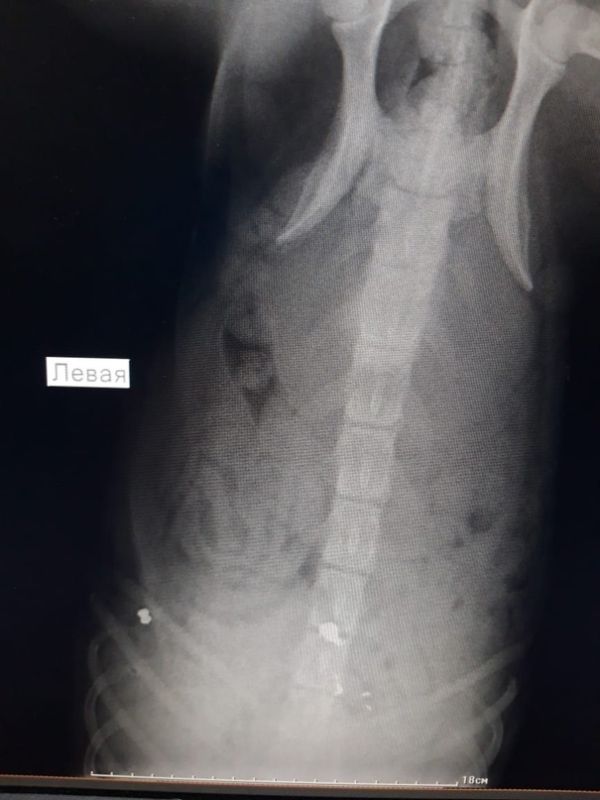

Окровавленную собаку нашли в районе домов № 23, № 25 на улице Алексеева. Пёс не мог самостоятельно передвигаться, и поначалу волонтёры подумали, что его сбила машина. Однако рентген показал, что в позвоночнике и в бедре животного застряли две пули.

Бобик жил у лицея № 4 и часто играл с детьми. Сейчас он в ветеринарной клинике Воронежа. Врачи извлекли пулю из позвоночника пса, которая сильно повредила спинной мозг. Есть шанс, что животное будет ходить, так как у него сохраняется чувствительность в лапах. Вторая пуля пока не извлечена.